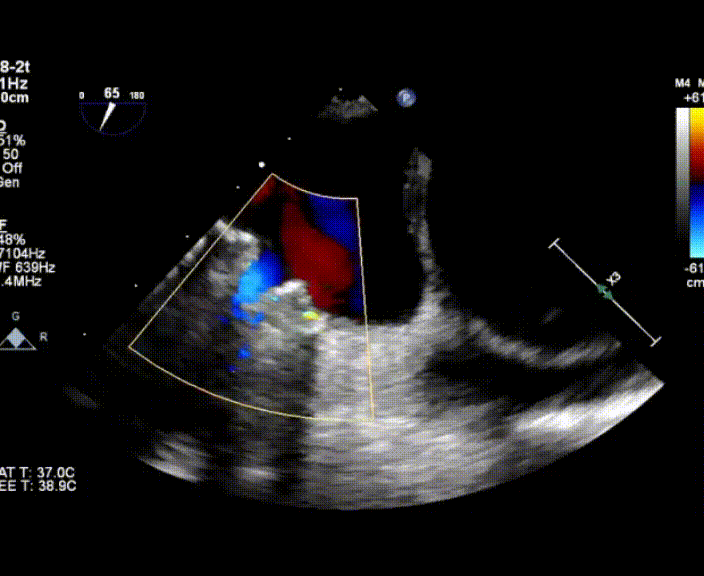

术中首先在局麻下穿刺股动脉、股静脉,完成心导管检查评估后转为全麻,在食道超声引导下穿刺房间隔,穿刺成功后将加硬导丝送入左上肺静脉建立轨道,根据患者病情行球囊预扩张后植入6mm孔径房间隔造孔支架,经透视及食道超声评估支架左右盘展开良好,夹持于房间隔两侧,固定稳定、位置良好,食道彩超显示房水平右向左为主分流,分流孔直径符合预期大小,心导管检查评估达到预期效果,释放造孔支架。术后12h患者下床活动,恢复顺利,拟于近日完善术后评估后出院。

图4.术后超声-房间隔可见分流束